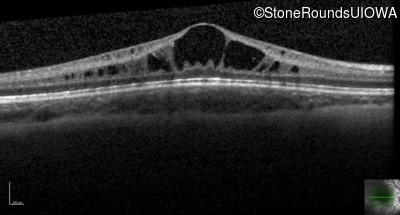

Optical Coherence Tomography - Left - 20/40

Exemplar / OCT Stack